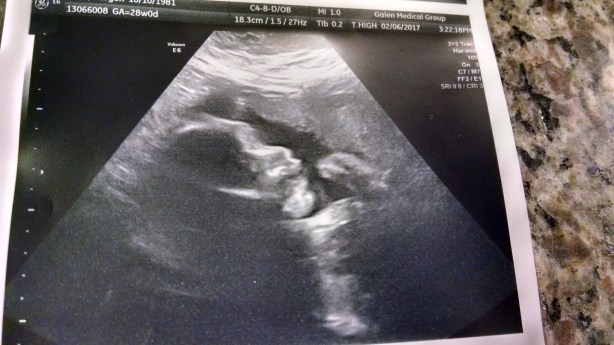

So I went to my 28 week appointment yesterday with my friend and coach Katrina (and Davis, who was very helpful) and had the glucose test (which wasn’t nearly as gross as everyone says it is) and an ultrasound. Kiddo is current head-up, and we got to see some little hands and a profile while the tech searched around for all the measurements that we didn’t get last time.

At 28 weeks I’m headed into the third trimester and am still holding strong at having only gained a few pounds, but there was some level of concern from the doctor because kiddo’s fluid looked low on this ultrasound and she’s small (13th percentile). So, with no discussion allowed, I’m currently grounded from the gym (or walking on the treadmill or yoga or any of the other things I suggested I might go and do) and have been instructed to “sit on the couch and drink water – period.” While the majority of the other items looked fine, I’ll be headed to see a high risk doctor this coming week to get a second opinion. My doctor said that she wasn’t super worried about it, but did think it was time I took it easy on purpose and wanted to make sure everything was alright.